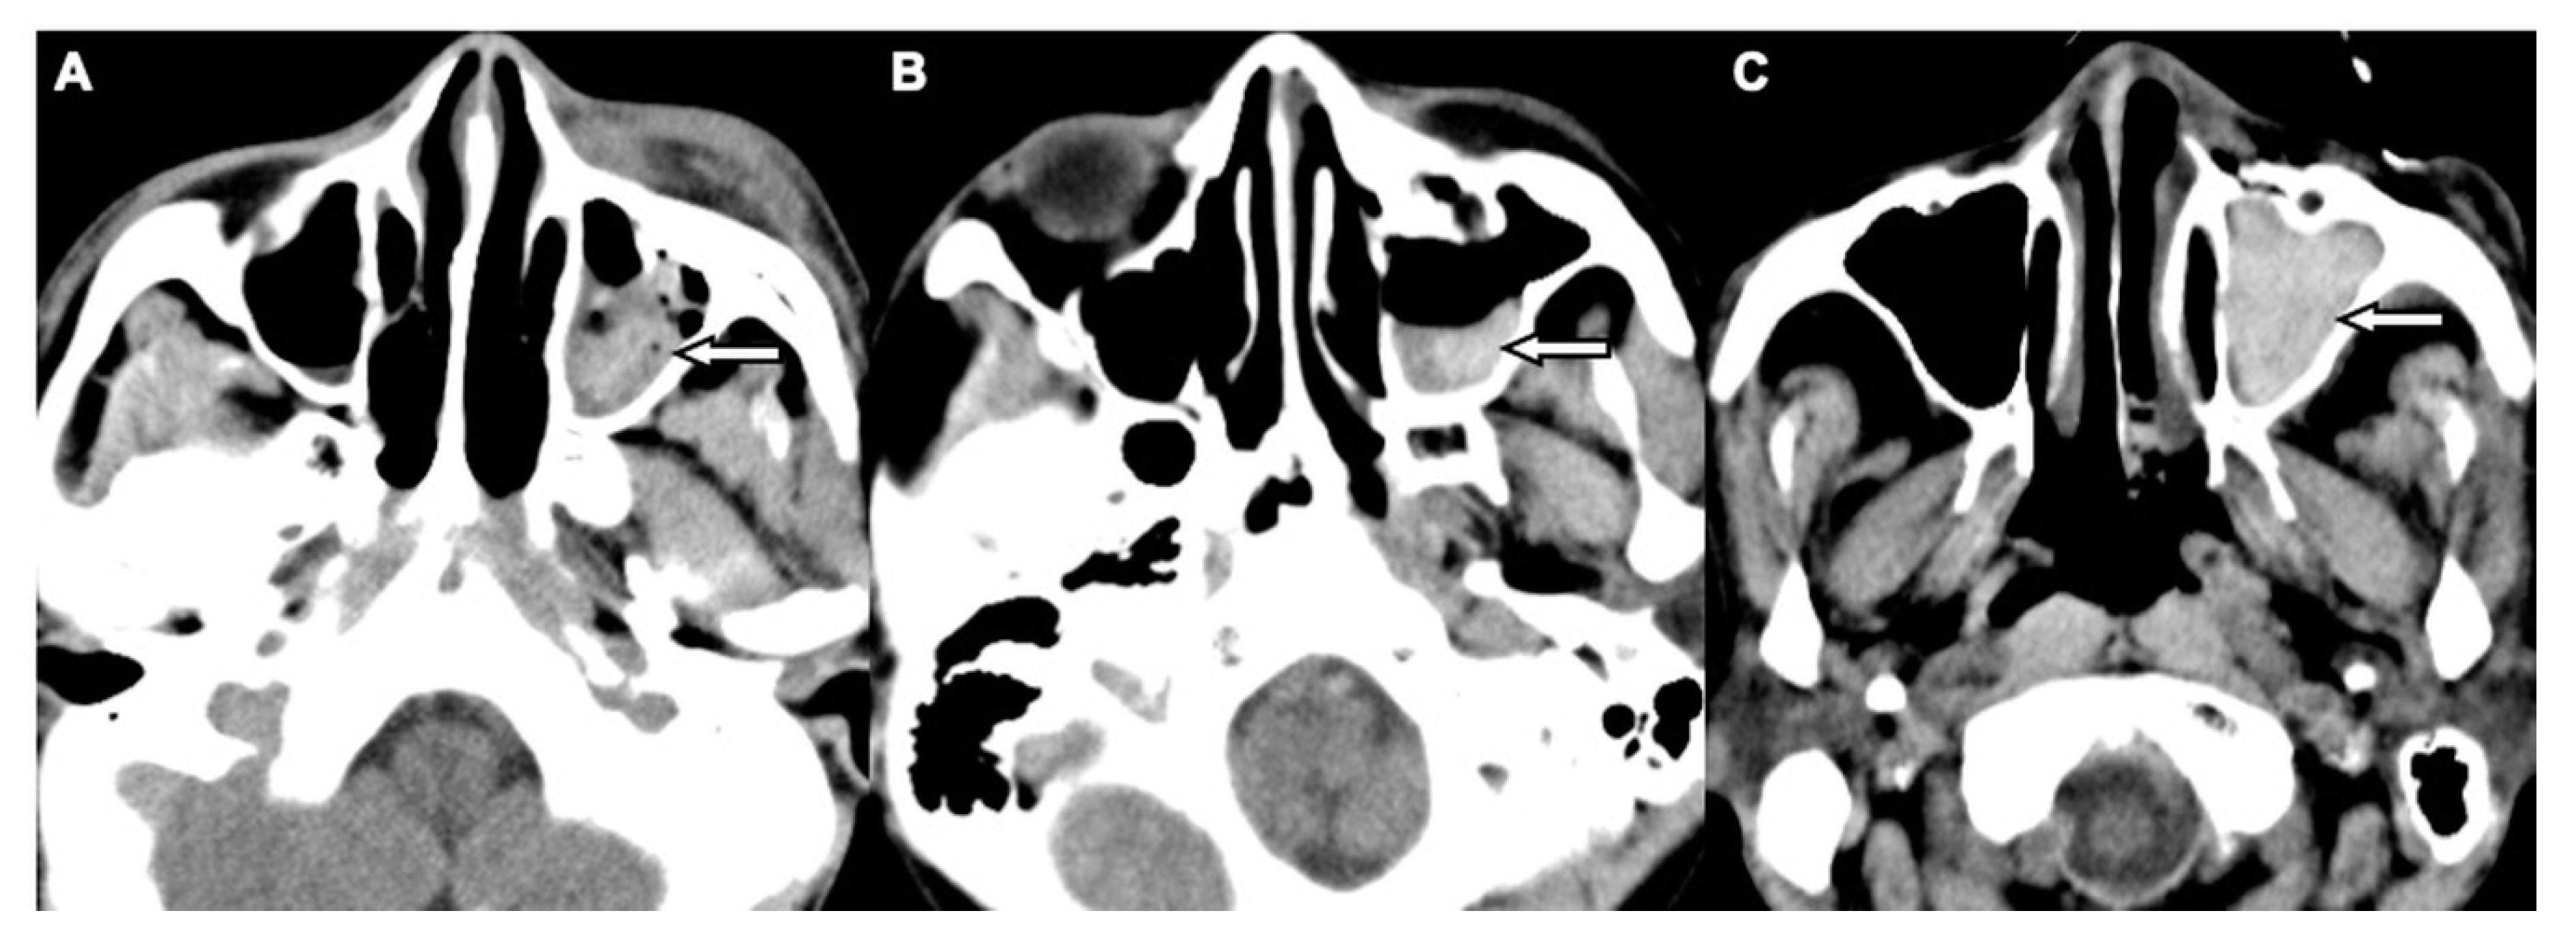

| MHS | 188 (94.9) | 197 (5.9) | <0.001 |

| MHS type 1 | 141 (75.0) | 7 (6.9) | <0.001 | 47.50 (8.26–273.05) |

| MHS type 2 | 44 (23.4) | 63 (61.8) | <0.001 | - |

| MHS type 3 | 3 (1.6) | 32 (31.4) | <0.001 | - |